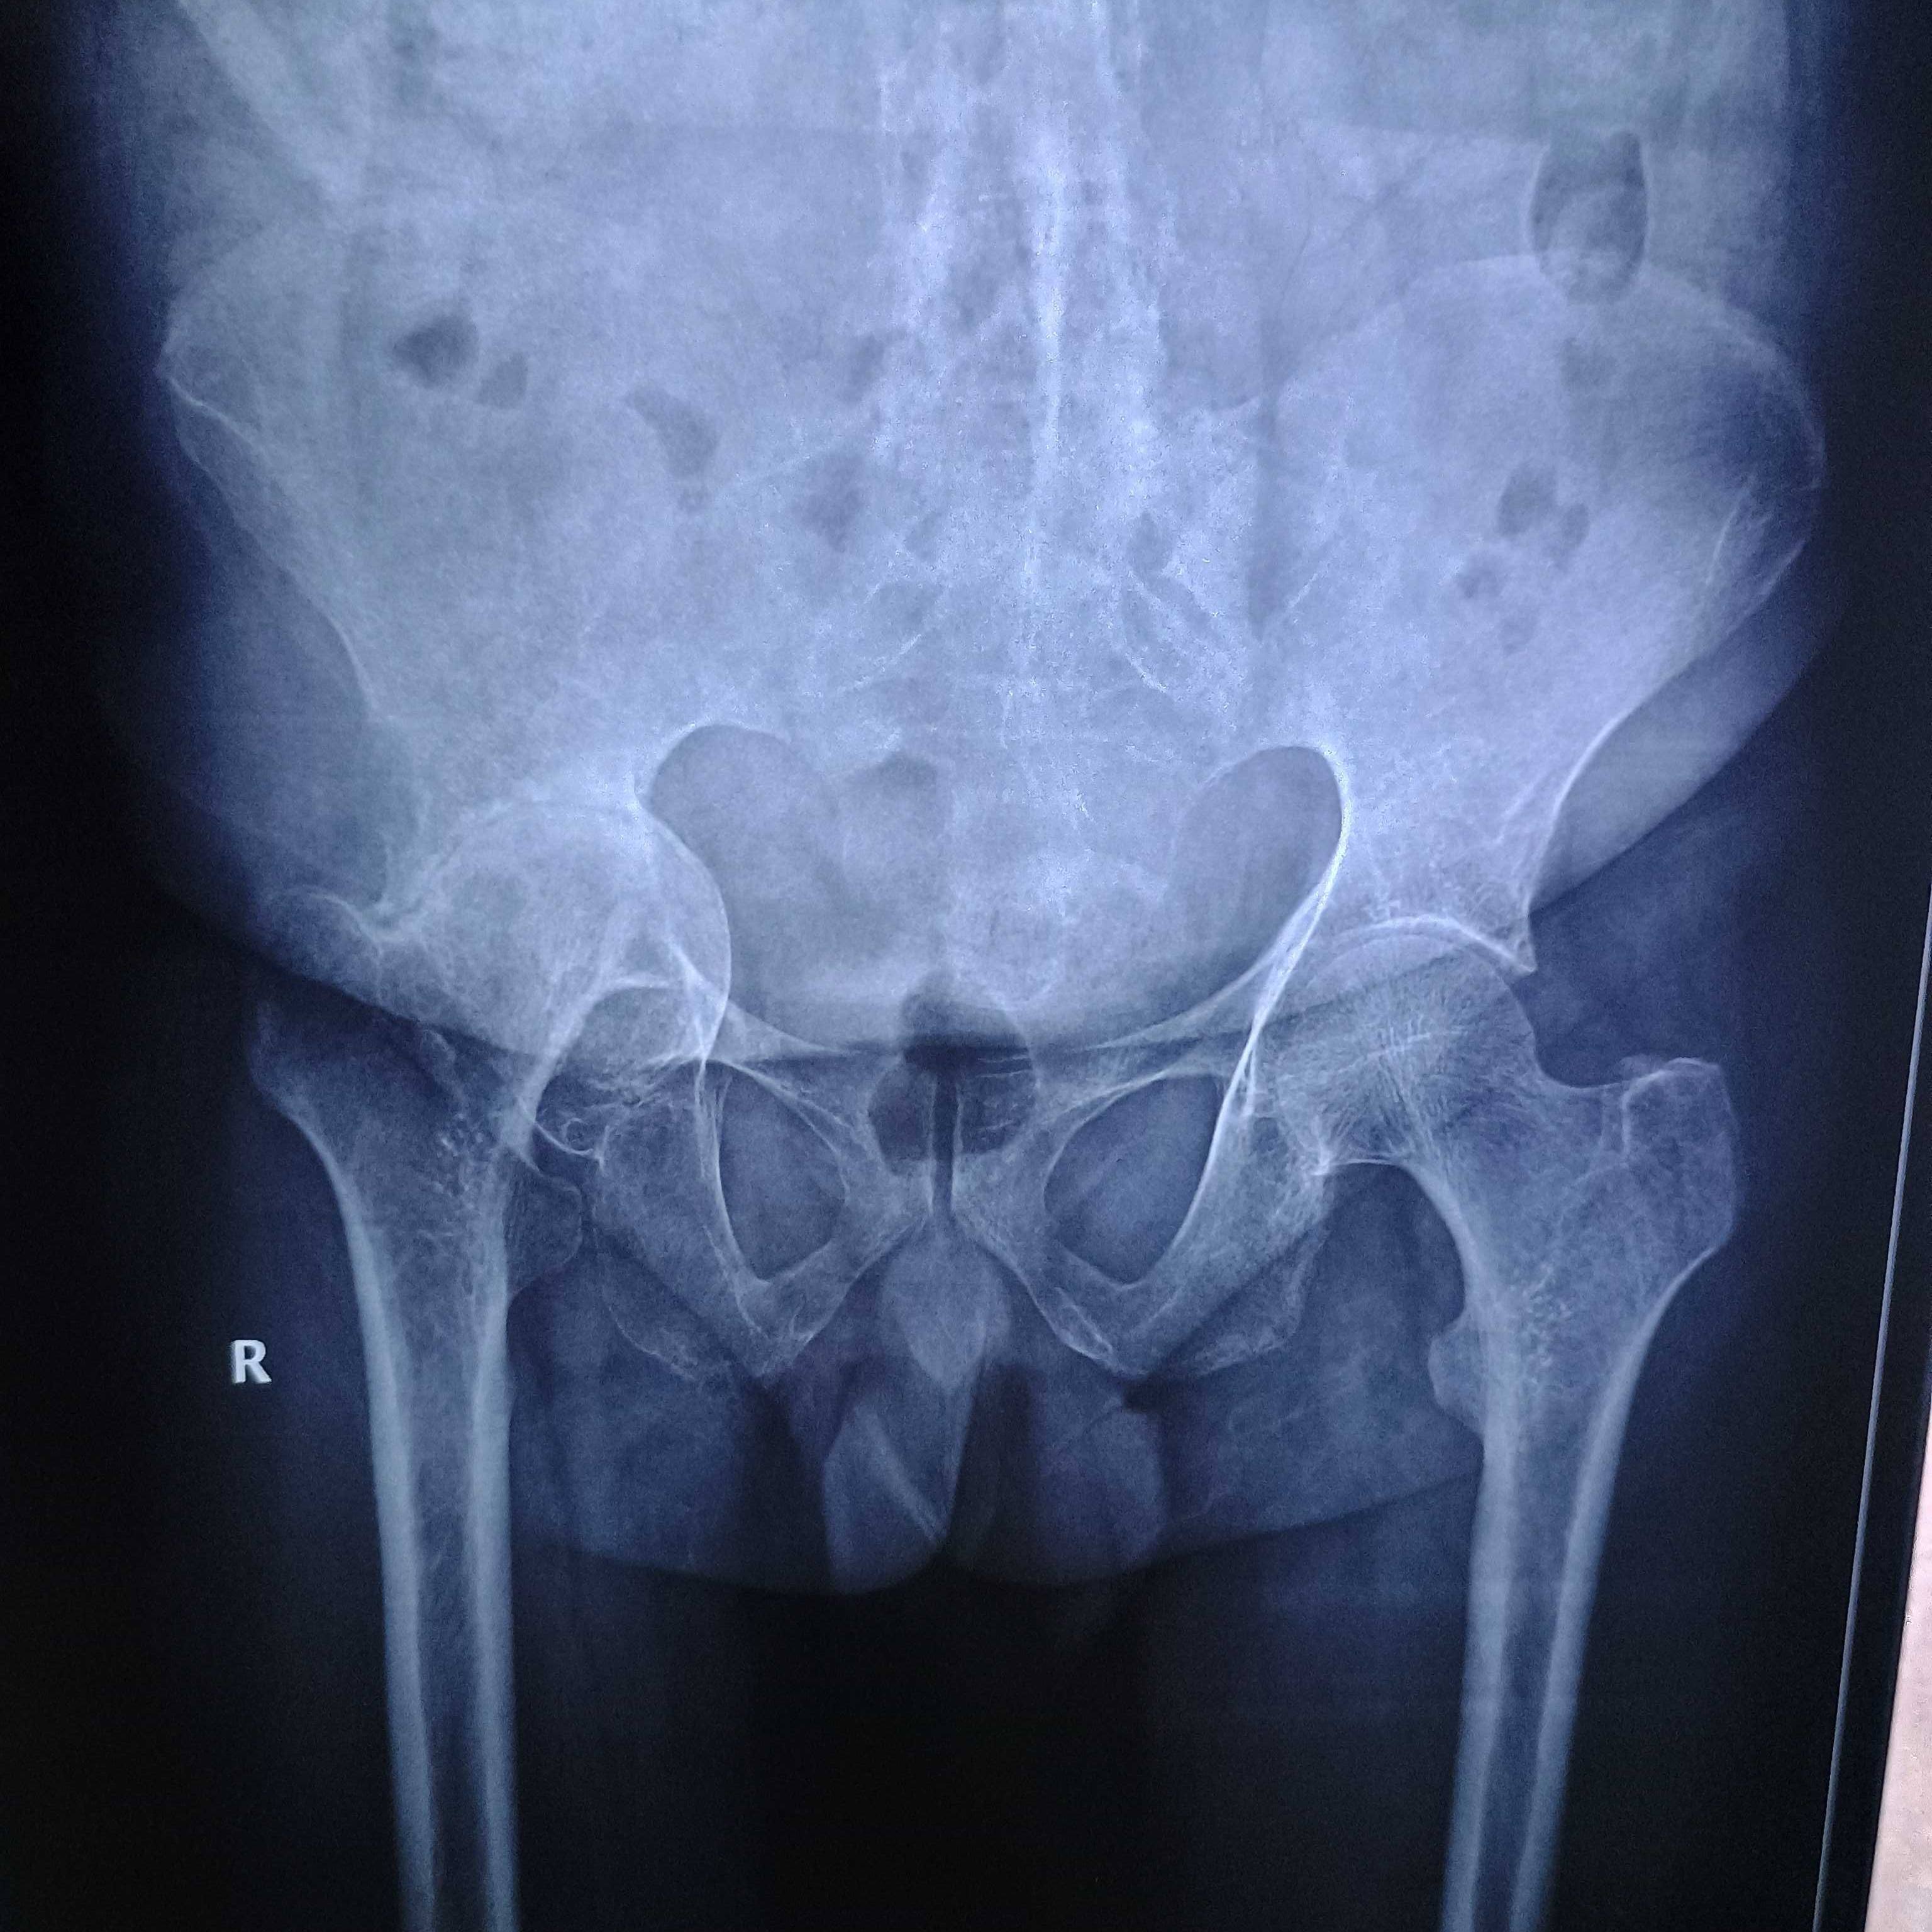

Dr Sir, AVN 3rd stage in both shoulders due to steroids used during COVID treatment and also having bilateral in hip joint 2nd and 3rd stage. 1. Can undergo bilateral hip replacement 2. How to manage with a paining shoulder after hip replacement 3. Or need treatment for shoulders first after sometime for the hips..